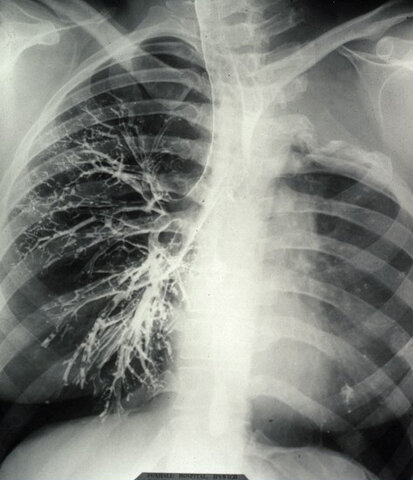

Tuberculosis(TB) is a disease that affects the lungs and other organs. This disease can be transmitted through air particles or some bodily fluids like blood, saliva etc. The bacteria that TB is made up of is from a group called mycobacterium. there are 54 subspecies of bacteria in this group.

Symptoms included a general unwell feeling(weak, fever and nauseous), fatigue and weight loss, persistent coughing for weeks on end(in bad cases blood would be coughed up). finally In rare circumstances TB can affect the brain, kidneys, skin, bones, joints or lymph nodes.

Collapse therapy was just being introduced. It was experimental and not yet universal. Collapse therapy is when parts of the ribs are removed in order to collapse the infected lung. This gave the lung time to rest and heal. Since this method was expensive and very dangerous at the time people often had to find other ways. Most doctors just recommended lots of rest and healthy eating habits. There was also medications being tested. At the time those drugs were often more hurtful than helpful.